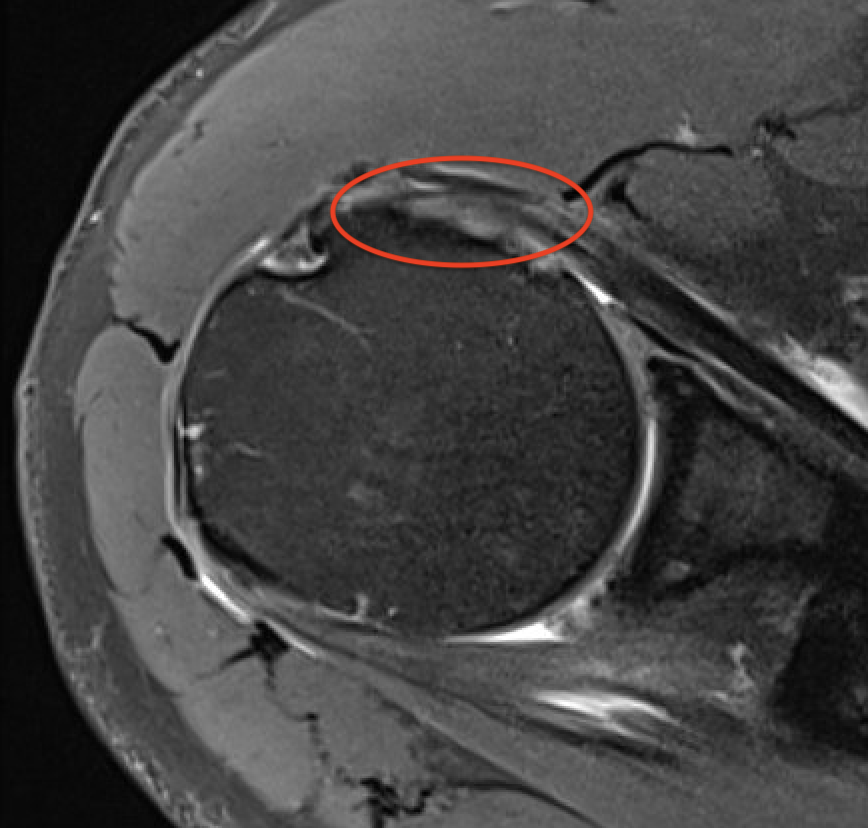

Full thickness retracted subscapularis tear

Full thickness retracted subscapularis tear with medial dislocation of long head of biceps tendon